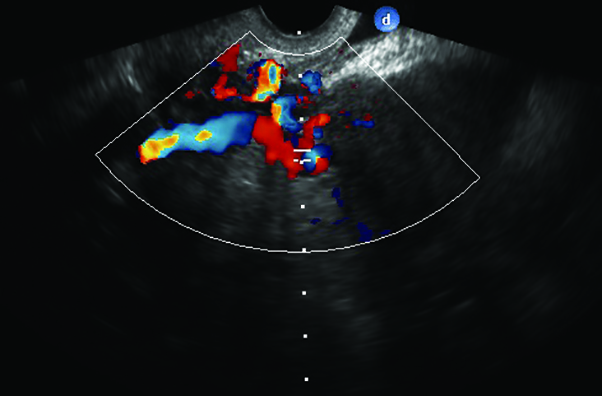

Fig. 4. Flebografia que demuestra desarrollo de várices uterinas y gonadal izquierdas, como consecuencia de la compresión venosa renal izquierda.

Se corrobora el diagnóstico presuntivo con flebografía observándose compresión de la vena renal izquierda entre la aorta y la arteria mesentérica superior y el consiguiente desarrollo de varices uterinas y ovárica izquierdas (Fig. 4).